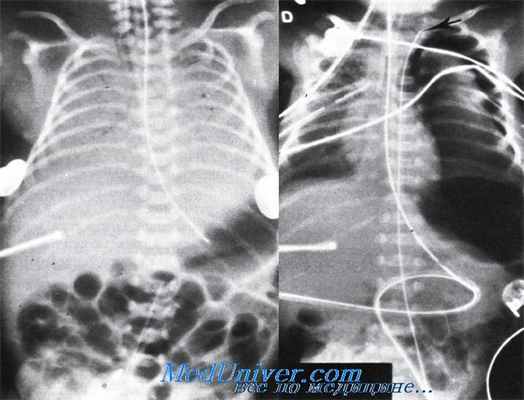

Различные неправильные положения катетера в пупочной артерии: слева — близость к почечным артериям на уровне II поясничного позвонка; справа — катетер в левой плечеголовной артерии.

Различные неправильные положения катетера в пупочной артерии: слева — катетер в правой плечеголовной артерии; справа — катетер в тазовой артерии.